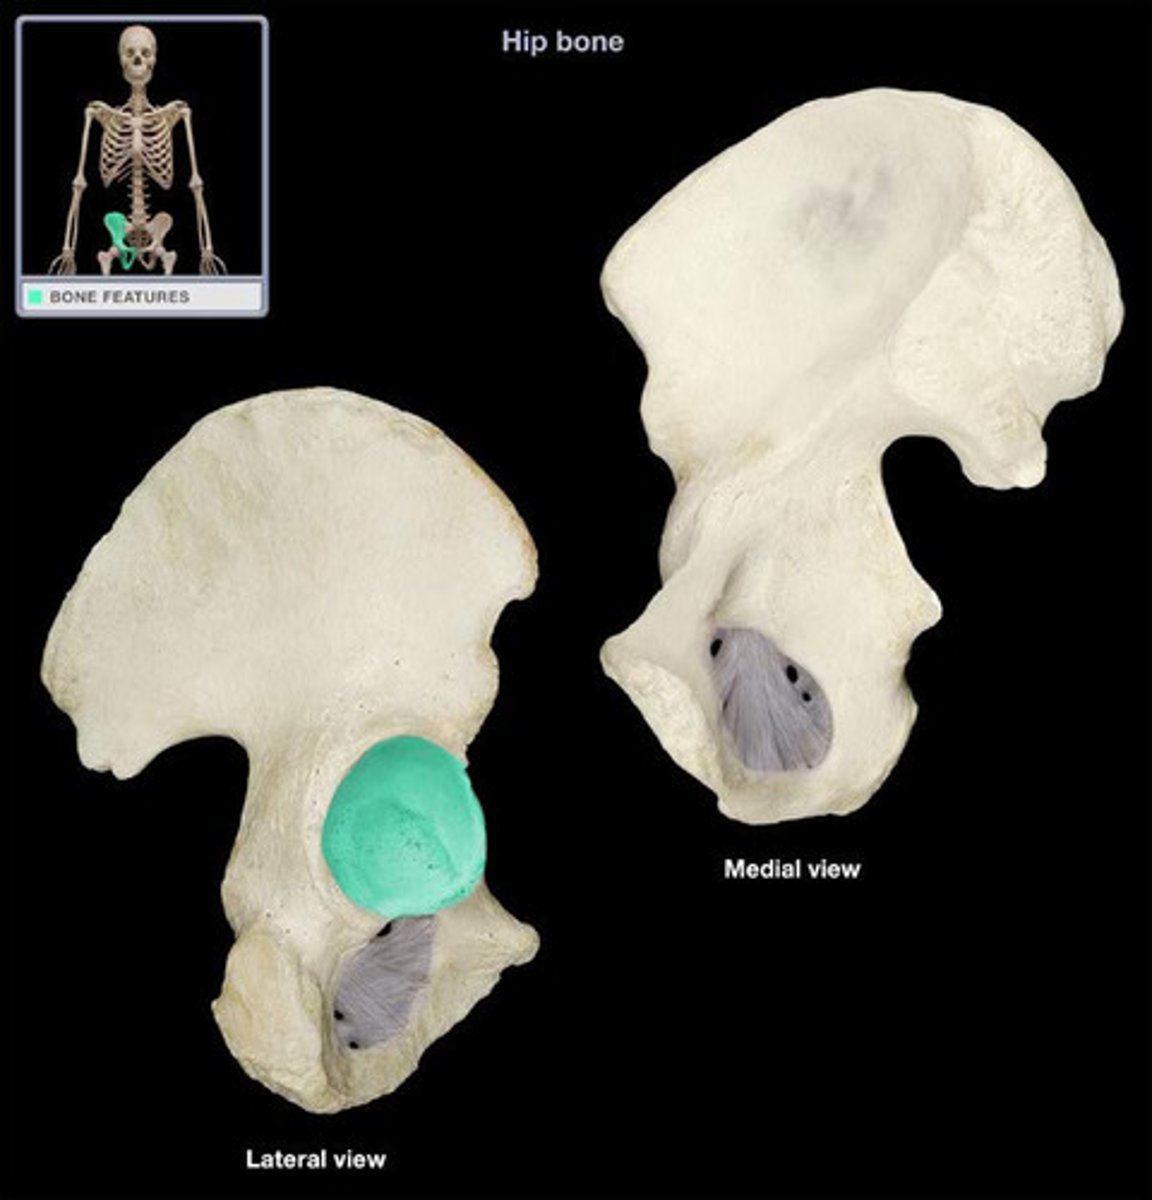

Acetabulum

large socket in the pelvic bone for the head of the femur

iliac fossa

The broad, slightly concave inner surface of the ilium.